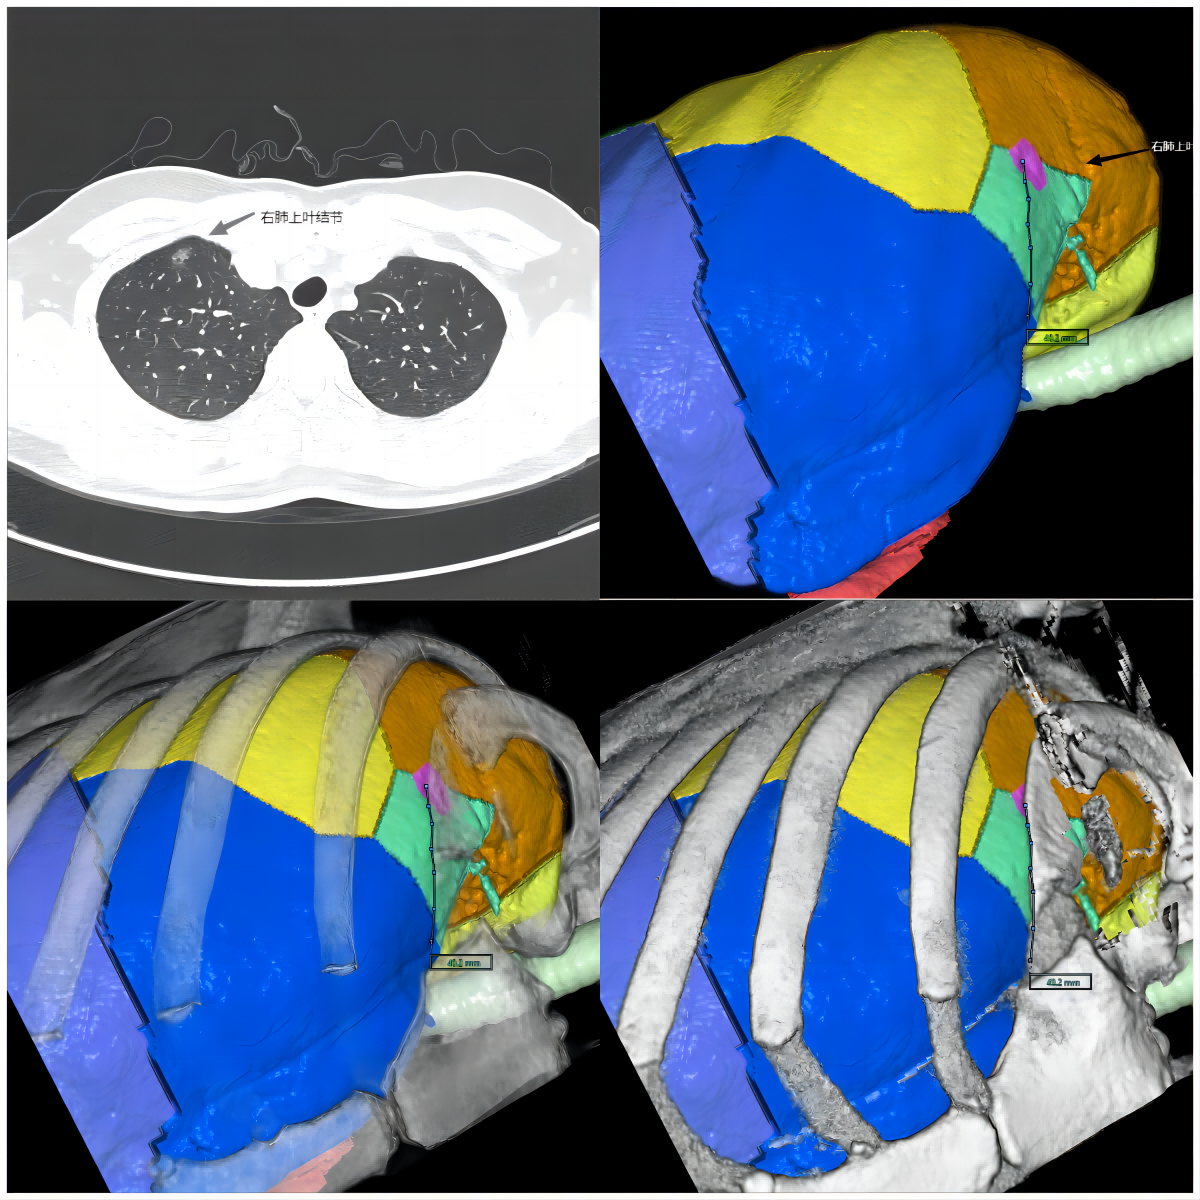

随着人们生活水平和健康意识的不断提高,胸部CT体检筛查的逐渐普及,肺结节在人群里的筛出率在不断攀升,很多患者发现肺部结节后非常的担心,害怕是癌症,也害怕手术带来的不适感或者创伤,这种恐惧感有时候会影响患者的抉择,有时候无法做出正确的选择,甚至错过手术治愈肺结节的时机。希望通过这篇科普文章能够解答罹患肺结节病友们的疑问以及给出一些指导性意见,让他们/她们能够勇敢地与肺结节做斗争。

关键词肺结节  快速康复  胸腔镜  单孔  无管手术